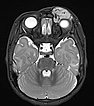

T2-gewichtete axiale MRT mit Fettsättigung. Die Raumforderung medial am linken Auge ist relativ homogen hyperintens und scharf abgrenzbar zum umgebenden Rand. Als Zeichen der starken arteriellen Durchblutung sieht man einige schwarze, signallose arterielle Gefäße in der Läsion („flow voids“). Auch dies ist typisch für ein infantiles Hämangiom.

T2-gewichtete axiale MRT ohne Fettsättigung. Die Raumforderung medial am linken Auge ist auch hier relativ homogen hyperintens und zeigt zentrale flow-voids. Aufgrund der fehlenden Fettsättigung ist die Raumforderung aber nicht so gut vom umgebenden Fettgewebe abgrenzbar.